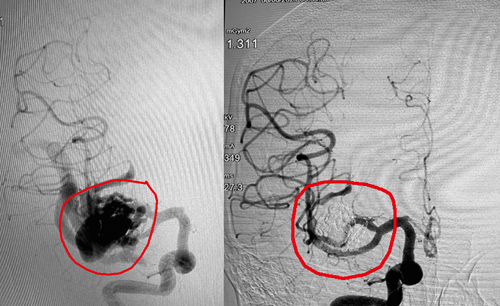

图五图六的线圈栓塞术,是借由导管将白金线圈送入动脉瘤中将其填满。数月后,血管内膜会增生和复盖动脉瘤开口。

动脉瘤的形状不一,若长得像榴梿,顶部有细柄,线圈在塞满之后就不会移位;若长得像杯子,开口较大(如图五),单纯使用线圈栓塞术可能会发生移位,造成血管阻塞引发中风,因此需要搭配球囊或支架,以将线圈固定于动脉瘤内。

此个案中所搭配的是球囊,并且会在栓塞完成后随导管移出;若所搭配的支架则不会取出。